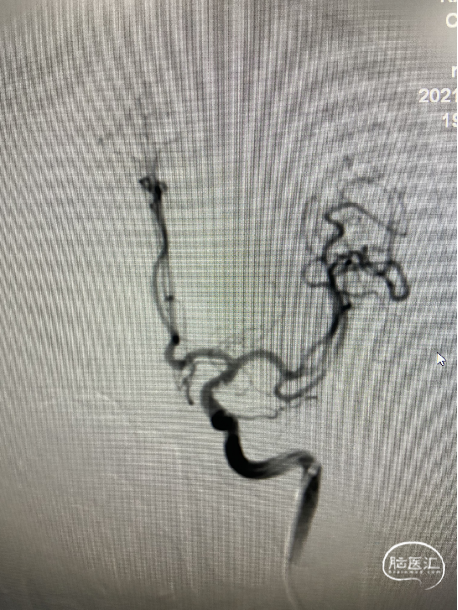

工作位+路图下Synchro-0.014in×200cm微导丝携带PROWLER SELECT PLUS微导管送至右侧大脑中动脉M2段远端,微导丝携带Echelon-10微导管送至M1段动脉瘤体内。经PROWLER SELECT PLUS微导管释放ENTERPRISE2 4.0mm×16mm,覆盖瘤颈,经Echelon依次填入强生ORBIT GALAXY 3mm×6cm弹簧圈成篮,继续填入ev3 2.5mm×6cm,1mm×2cm,1mm×1cm弹簧圈,造影示M1段动脉瘤填塞完全,造影剂滞留。

调整工作位角度,路图下Synchro0.014×200cmm微导丝携带SL-10微导管送至右侧颈内动脉,再用微导丝携带Echelon-10微导管送至C7动脉瘤瘤体内,经Echelon-10半释放强生ORBIT GALAXY 3mm×8cm弹簧圈,经SL-10释放Neuroform Altas 4.0mm×21mm支架,覆盖瘤颈,继续填塞第一枚弹簧圈,造影示支架位置满意,继续填塞强生ORBIT GALAXY 2mm×6cm弹簧圈,ev3 1mm×3cm,1mm×2cm弹簧圈,复查造影示动脉瘤栓塞致密,载瘤动脉通畅,复查颅内正侧位造影右侧颈内动脉、大脑前动脉、大脑中动脉显影良好。

经PROWLER SELECT PLUS微导管释放ENTERPRISE2 4.0mm×16mm,覆盖瘤颈,经Echelon依次填入强生ORBIT GALAXY 3mm×6cm弹簧圈成篮,继续填入ev3 2.5mm×6cm,1mm×2cm,1mm×1cm弹簧圈,造影示M1段动脉瘤填塞完全,造影剂滞留。

路图下Synchro0.014×200cmm微导丝携带SL-10微导管送至右侧颈内动脉,再用微导丝携带Echelon-10微导管送至C7动脉瘤瘤体内,经Echelon-10半释放强生ORBIT GALAXY 3mm×8cm弹簧圈,经SL-10释放Neuroform Altas 4.0mm×21mm支架,覆盖瘤颈。

造影示支架位置满意,继续填塞强生ORBIT GALAXY 2mm×6cm弹簧圈,ev3 1mm×3cm,1mm×2cm弹簧圈,复查造影示动脉瘤栓塞致密,载瘤动脉通畅。

造影右侧颈内动脉、大脑前动脉、大脑中动脉显影良好。